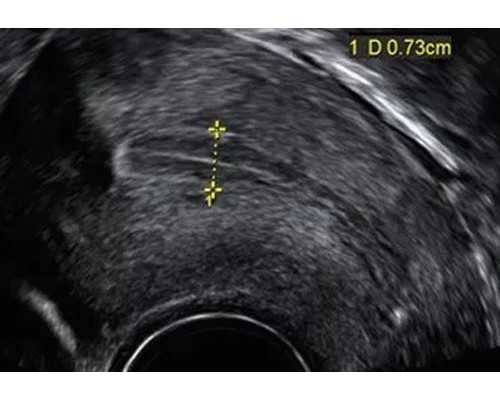

为了提高怀孕的概率,女性一定要通过各种不同的方式来监测排卵,排卵之后的同房能够迅速的提高怀孕的概率,而且在临床监测排卵的过程当中有很多不同的方法,在49岁试管成功双胞胎进行多方面实施的过程当中,这里有基础体温或者是血尿素的测定,还有各种B超以及宫颈粘液的评分,B超能够有效监测卵泡的发育,同时这也可以给我们带来最为准确的保障,因此能够连续动态的来直接观察整个卵泡的形态。